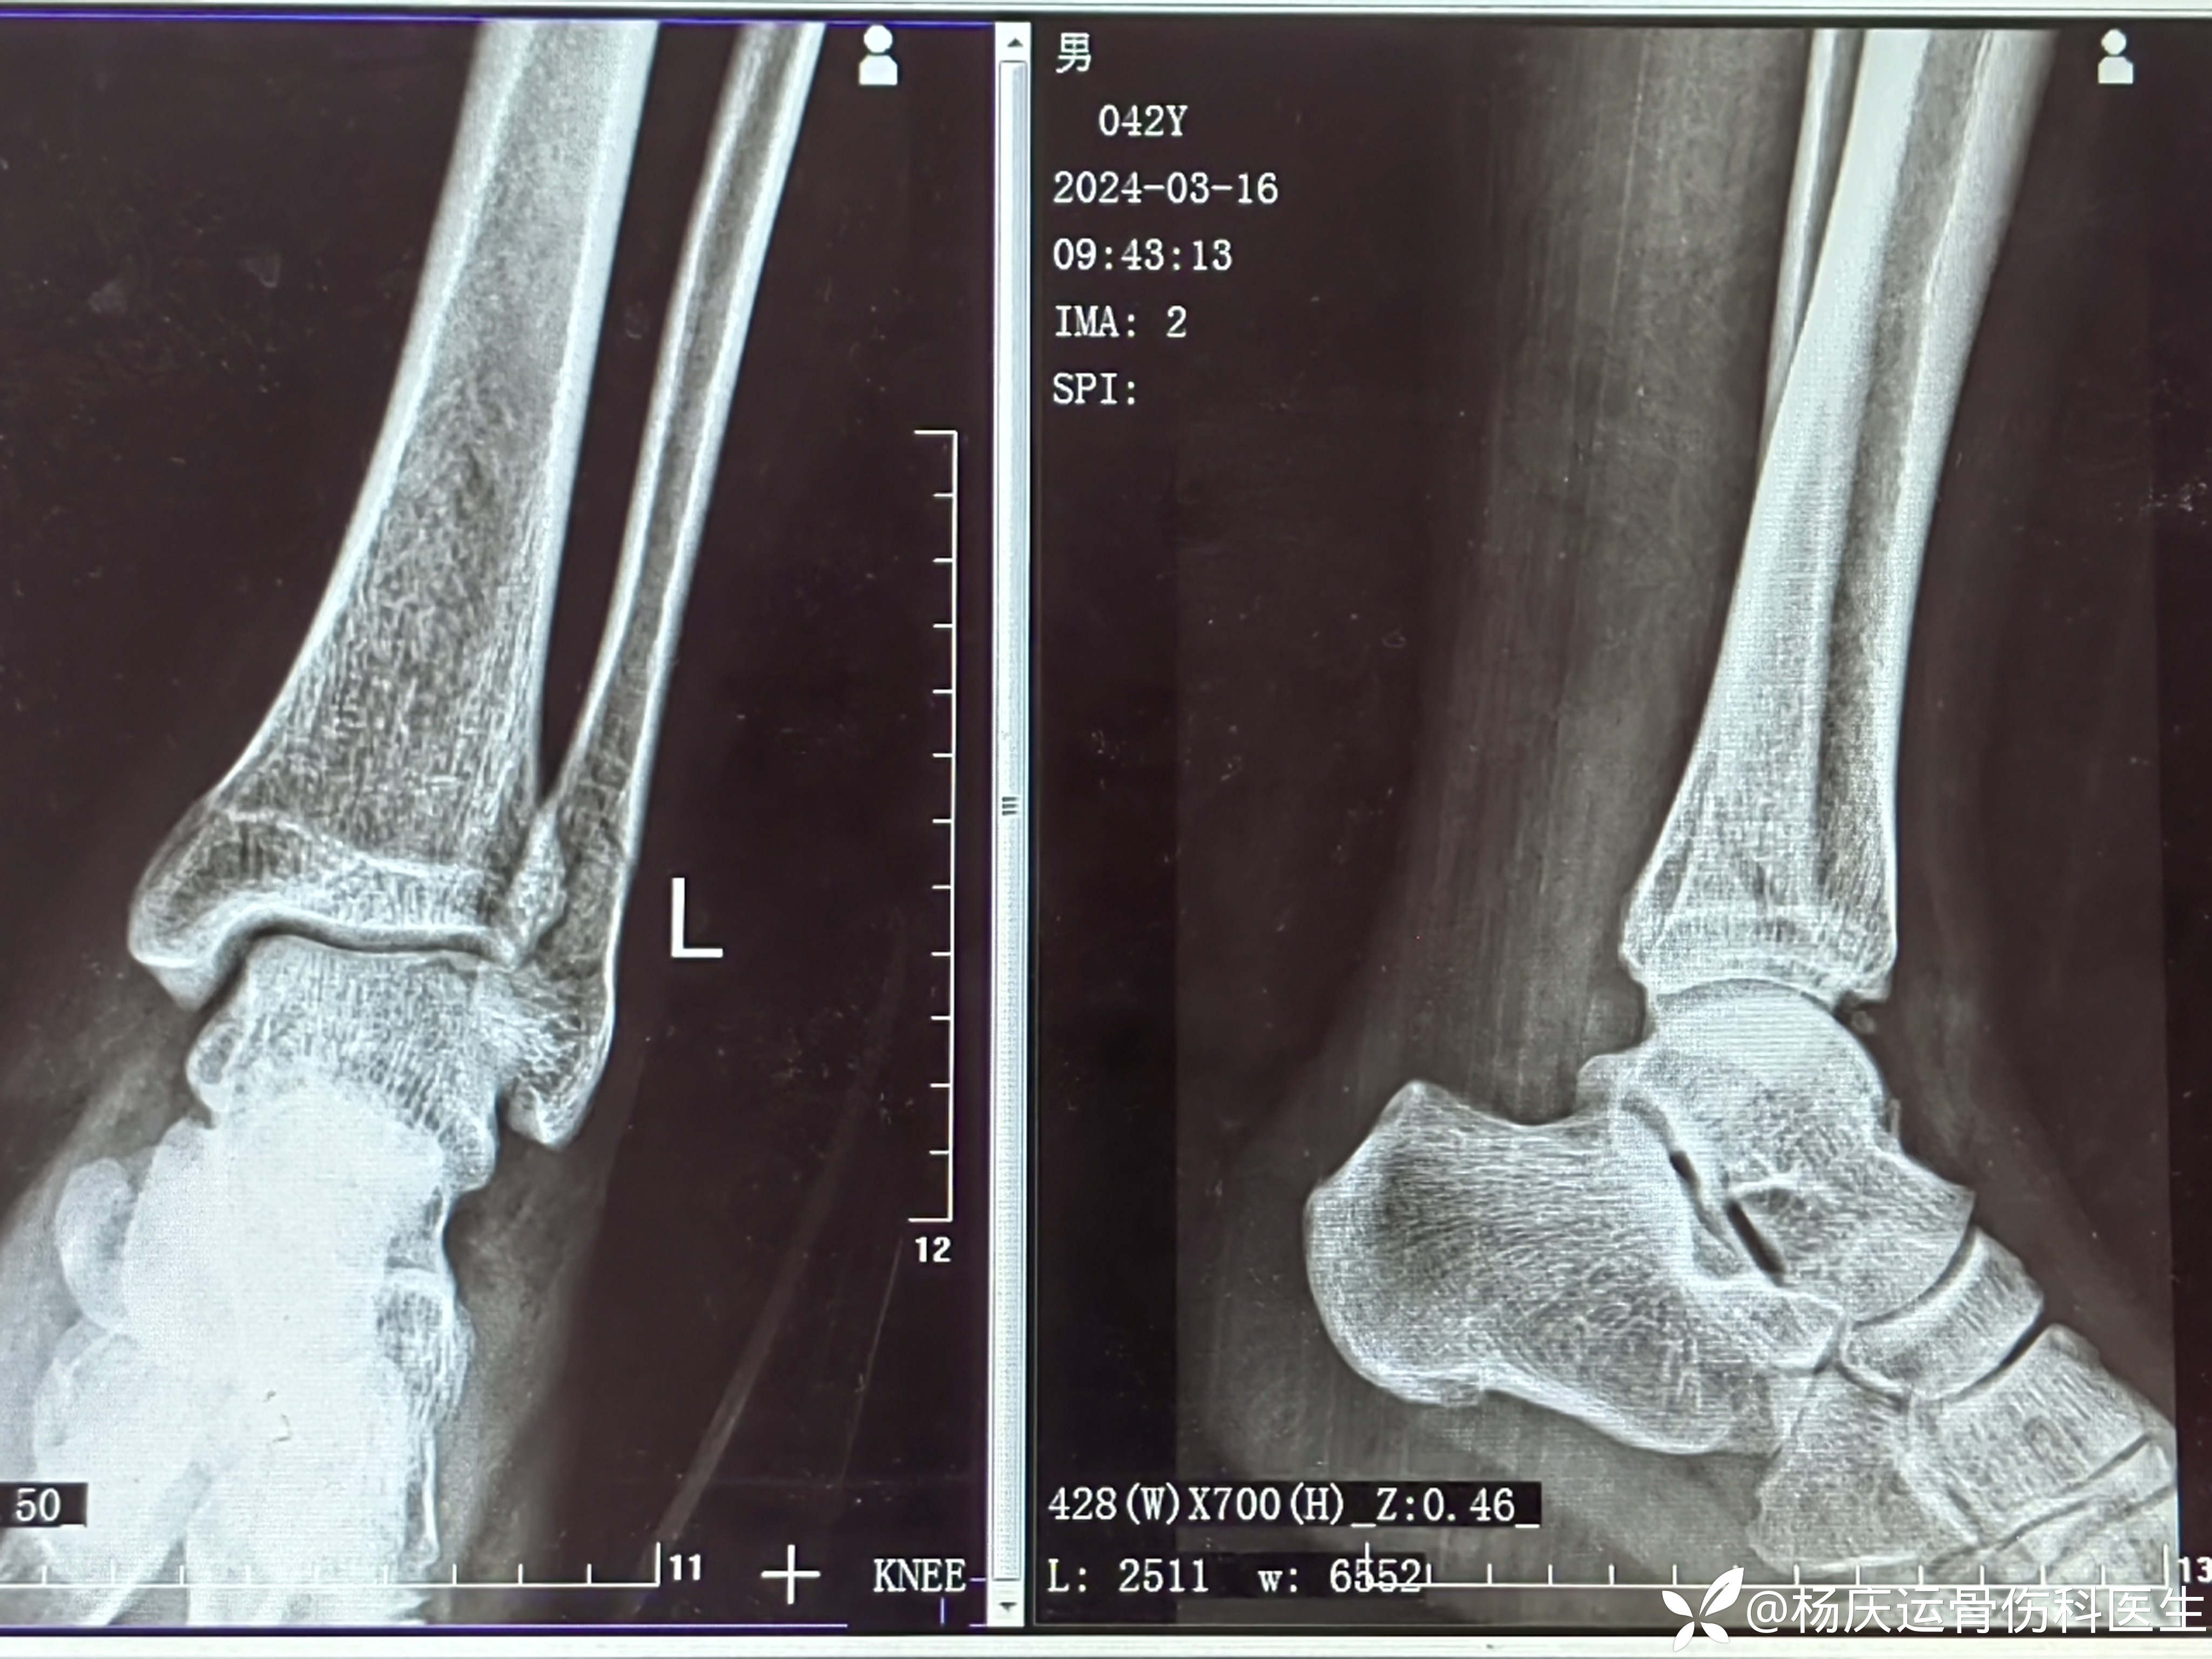

复位后

4天复查